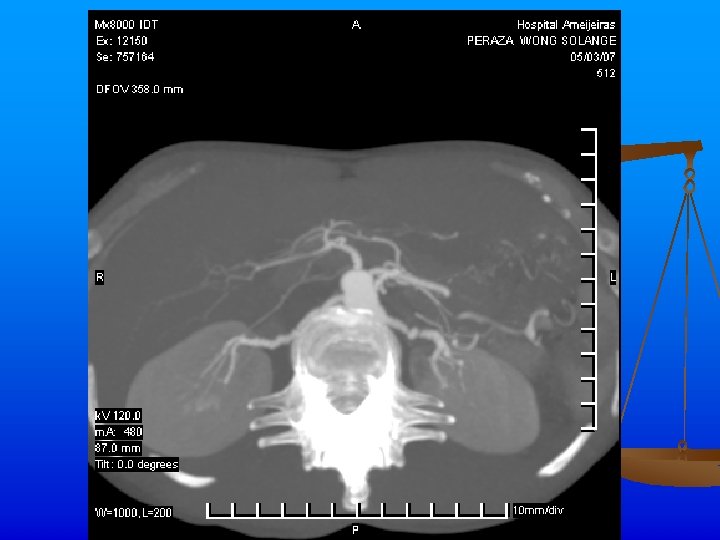

Exámenes Complementarios n n n Rx de tórax: Ligeros signos de hiperinsuflaciòn pulmonar. ICT normal. Índice de presiones de MI dentro de límites normales. Angio TAC: Se realiza angio. TAC abdominal inyectándose 120 ml de contraste, apreciándose áreas de estenosis y dilatación de ambas arterias renales, con un patrón arrosariado y zonas de hipoperfusión corticales en los polos de ambos riñones. Hay buena eliminación y concentración renal bilateral.